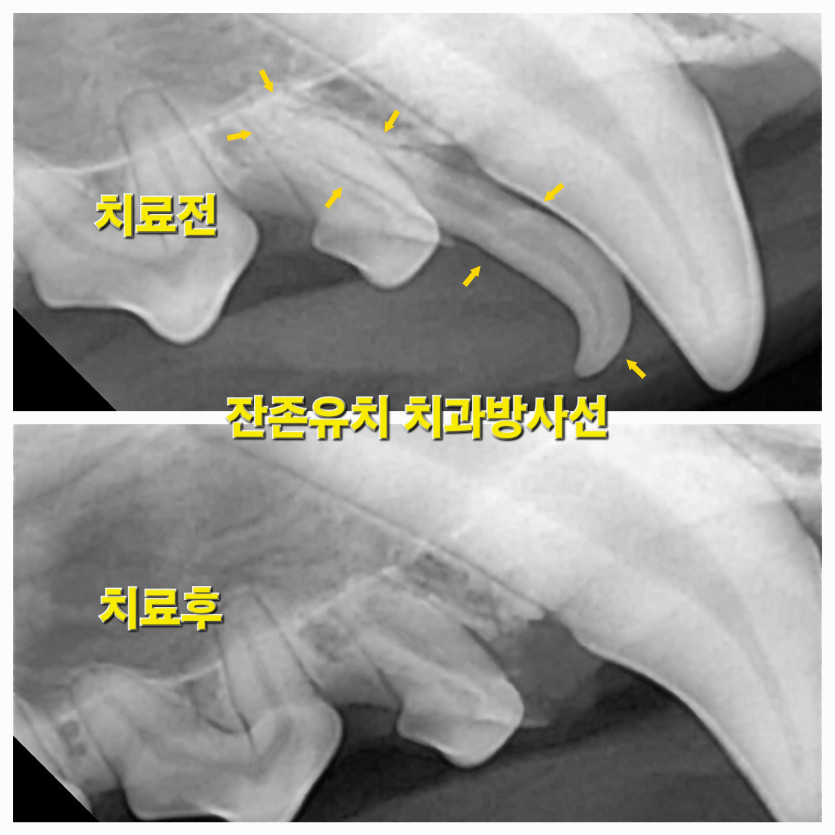

리오의 잔존유치 무통발치 치료후기

유치발치를 진행하였는데, 걱정하지 않게 아이 사진도 중간에 보내주시고 진행상황도 카톡으로 안내해주셔서 한결 걱정을 덜 한것 같다. 발치 수술도 잘 되었고 아이도 문제없이 회복했다.